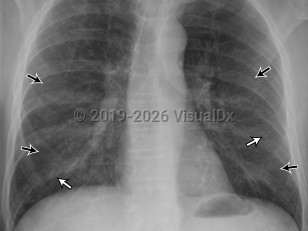

Pneumothorax

Spontaneous pneumothoraxSpontaneous pneumothorax